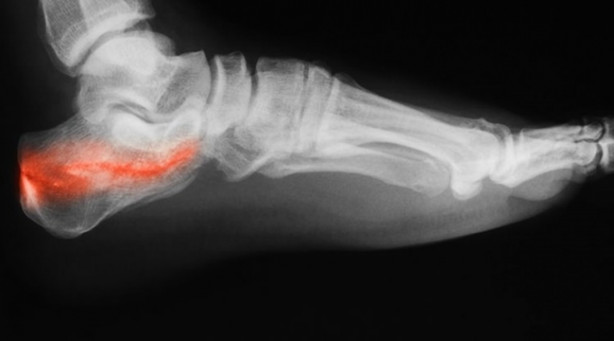

Topuk dikeninden en çok etkilenenler atletler gibi aktif spor yapanlar ya da topuklu ayakkabı giyenler. Topuk dikenine sahip olan kişilerin yaşadığı acı, birilerinin ayaklarına neşter batırması gibi tarif ediyorlar.

Uzun süre aynı yerde oturduktan sonra ya da sabahları kalktığınızda topuk dikenin acısını daha fazla hissedersiniz.

Topuk dikeni, aslında topuk kemiğinin alt kısmında diken benzeri çıntıya verilen bir isimdir.